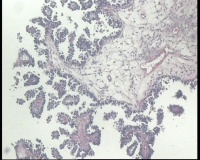

| 一般病史 | 彩超:盆腔可见囊实性回声,囊性为主,大小约5.0x3.7厘米,其内可见分隔回声,部分分隔内回声不纯净,形态欠规整 | ||||

| 标本名称 | 腔镜下右侧卵巢囊肿手术 | ||||

| 大体所见 | 囊壁样组织5.5x5.0厘米,4.5x2.5厘米2块,壁厚0.1-0.2lm,囊壁大部分光滑,局灶见0.7x0.5x0.3厘米淡黄色突起组织,另见淡黄色、肉粉色质软组织2.8厘米一堆。 | ||||